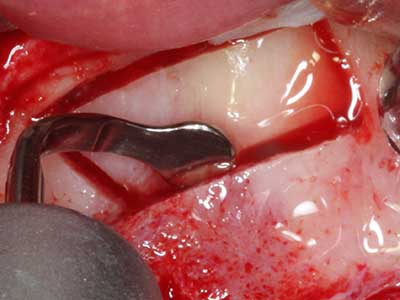

When surgical procedures are performed on bone in the immediate vicinity of sensitive structures such as blood vessels or nerves, rotary instruments pose a significant risk of iatrogenic injury. Piezoelectric devices can be helpful for preparation of bone covers and removal of hard tissue close to nerves, particularly for exposure of nerves after iatrogenic injury but also during nerve lateralization for resective and reconstructive procedures or implant placement (Fig. 17-20). Light contact between the piezotip and the nerve does not generally result in damage but proceeding incautiously with saw-like motions or attachments where a residual bone substrate remains may cause temporary or even permanent nerve damage. However, the risk of damage is considered to be substantially lower than when using saws or milling instruments (Pereira, Gealh et al. 2014).